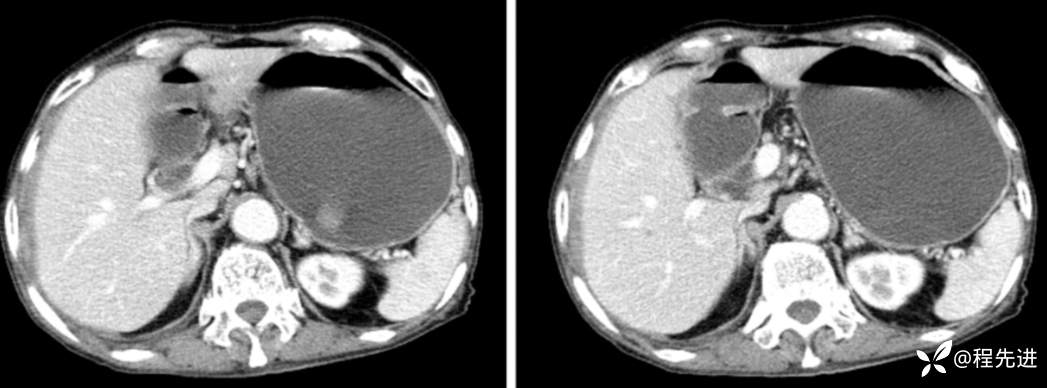

门脉期

延迟期